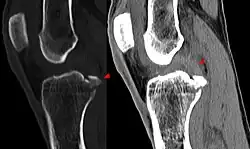

Procédés d'imagerie

Le diagnostic peut être confirmé par imagerie (IRM). Mais il faut noter que l'interprétation de l'IRM seule pour le diagnostic de rupture de LC conduit à 20 % de faux diagnostics. Cela dépend des images de coupe et de la position appropriée du genou pendant l'IRM. Le radiologue doit connaître avec précision les circonstances qui ont conduit à la blessure, et avoir aussi une bonne expérience de l'étude d'une articulation blessée, pour éviter les faux diagnostics. Pour comparer avec l'IRM, le taux d'erreur du test de Lachman, bien plus simple à accomplir, n'est que de 10 %[108],[109],[110],[111]. L'IRM est donc généralement moins sensible et moins spécifique que l'examen clinique par un orthopédiste qualifié[112]. Le résultat de l'IRM n'a que relativement rarement une influence sur la formulation finale du diagnostic[113] et ne devrait pas servir de remplacement pour une anamnèse soigneuse et la palpation[114]. Plusieurs études arrivent à la conclusion que l'IRM n'a de sens que pour des blessures complexes difficiles à expliquer, et là, pour éviter de poser un diagnostic négatif[115],[116],[117].

Les radios n'apportent aucune contribution immédiate au diagnostic de rupture de LC. Les deux LC sont invisibles à la radio, déchirés ou non. La seule utilité de la radio ne peut servir qu'au diagnostic des complications osseuses possibles.

Arthroscopie diagnostique

La sécurité diagnostique la meilleure est obtenue par arthroscopie diagnostique. Ce procédé représente l'étalon-or pour le diagnostic de la rupture de LC. Ce procédé relève d'une chirurgie invasive au minimum, mais comporte certains risques, comme toute intervention chirurgicale dans le genou du patient[118]. Comme cependant le traitement chirurgical d'une rupture de LC sera conduit par chirurgie arthroscopique, il est possible d'enchaîner celle-ci immédiatement après l'arthroscopie diagnostique, par la résection partielle du ligament (pour une déchirure) ou la reconstruction en cas d'arrachement. Avec l'accroissement de la facilité de l'IRM, le nombre d'arthroscopies purement diagnostiques a nettement diminué ces dernières années[119],[120]. L'arthroscopie diagnostique est quand même utilisée comme précédemment comme procédé de choix pour une compréhension certaine du diagnostic de rupture de LC, en cas d'examen clinique confus et d'IRM difficile à interpréter[118].